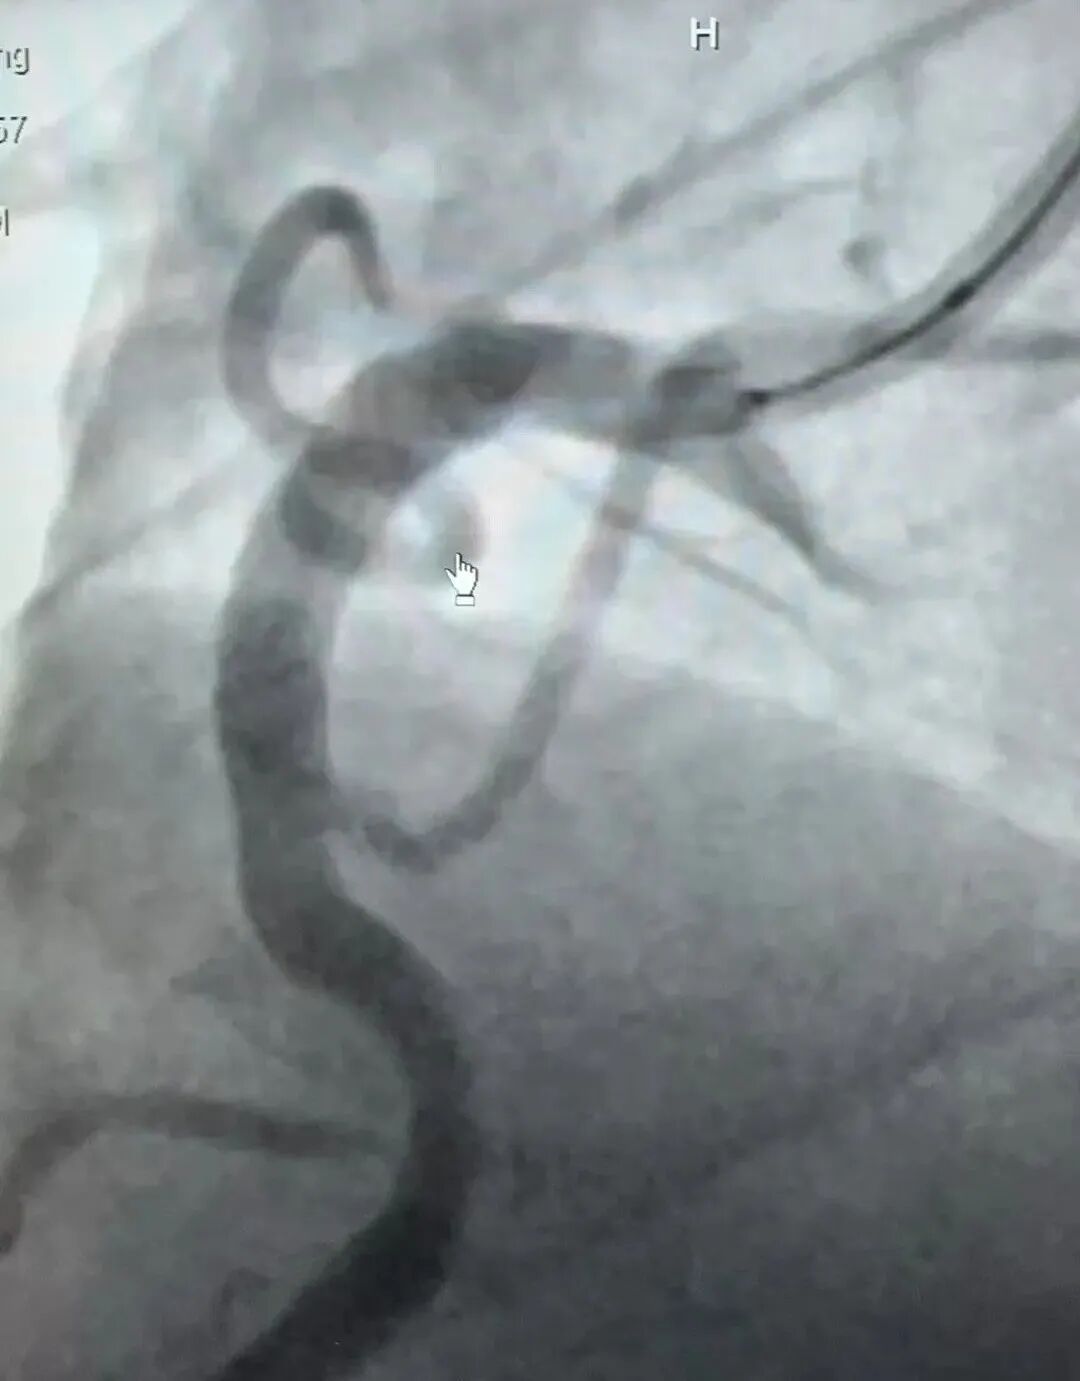

1.局部麻醉經(jīng)皮頸動脈球囊擴張成形術:該手術通過在頸動脈內(nèi)放置一個膨脹的球囊,擴張閉塞的血管,恢復正常的血流,有效解決左側(cè)頸內(nèi)動脈次全閉塞的問題。

2.腦保護傘下頸動脈支架置入術:在頸動脈內(nèi)放置一個支架,以維持血流通暢,為避免頸動脈粥樣硬化斑塊脫落引起腦梗塞,常規(guī)在腦保護傘下置入頸動脈支架是非常重要。

3.冠脈PCI術:通過在冠狀動脈內(nèi)放置一個支架,擴張狹窄的血管,恢復心肌的血液供應。冠脈PCI術是治療冠狀動脈粥樣硬化性心臟病的常用方法,可以有效緩解心絞痛等癥狀。